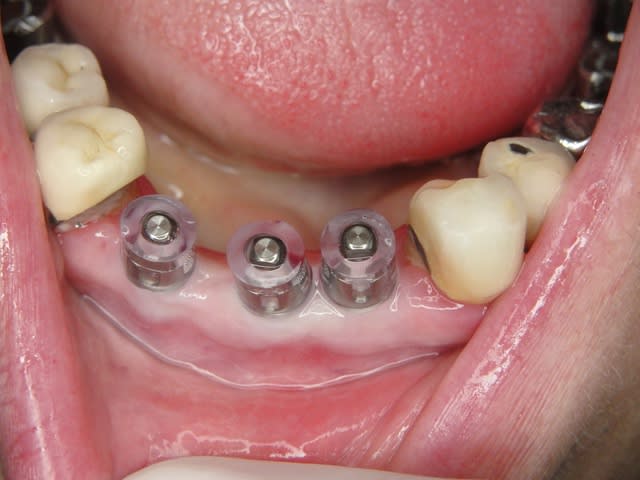

Maintenant concernant la demande de scans : je poste ce cas, une patiente vient me voir avec son scan car elle a consulté d'autres "spécialistes" et on lui refuse la pose d'implant secteur 4 où alors avec greffe préalable..Ca se discute..pas de temps à perdre je sais faire autrement..

Avec la chir trans gingivale technique MIMI ( Oui..un post sur la technique bientôt ..) j'ai pu placer deux 3,5/8mm..aurai je eu le meme résultat avec un lambeau..j'en doute..Les couronnes sont en titane. Recul clinique 2 ans ras. Simple efficace rapide moins onéreux satisfaisant pour le praticien et la patiente..